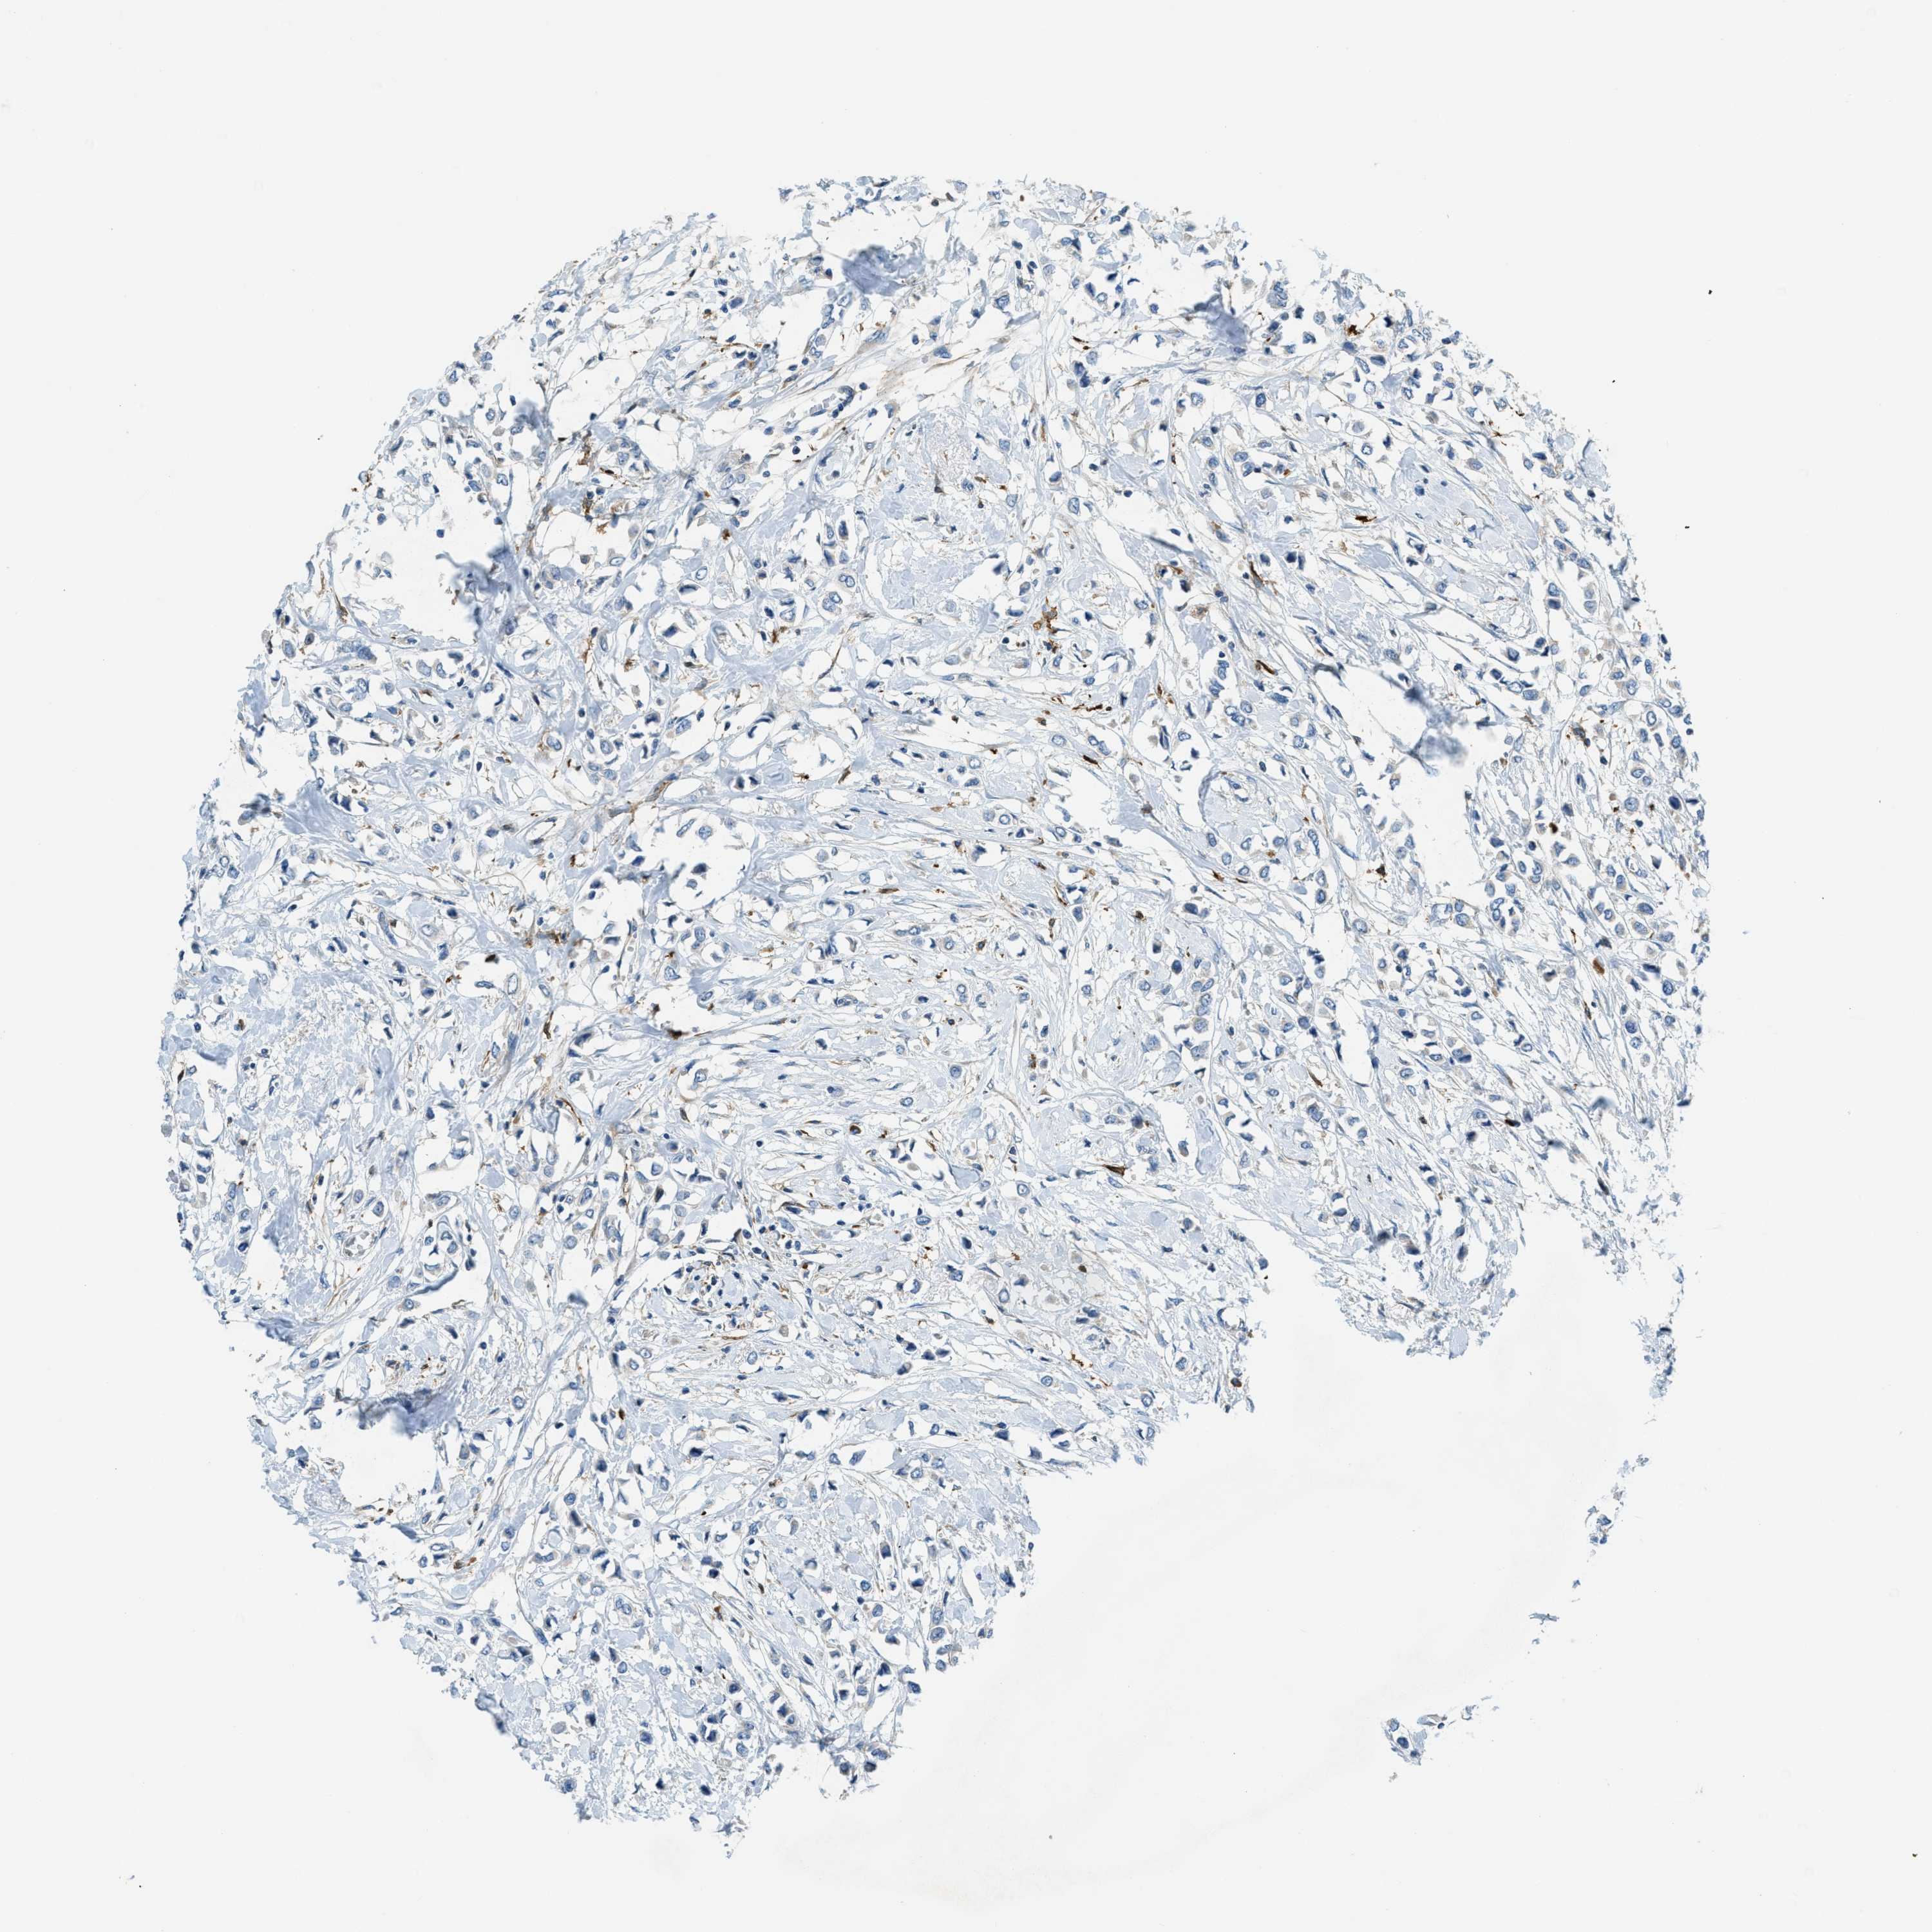

BRCA TCGA BRCA VALIDATION PROTEIN EXPRESSION

ANTIBODIES

AND

VALIDATION